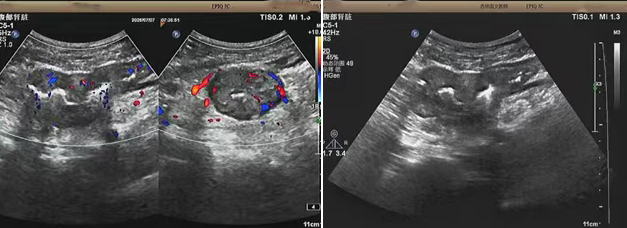

超聲檢查的結果進一步揭示了病情的細節(jié):下腹部偏左腸壁顯著增厚,原本清晰的層次結構遭到破壞,周圍脂肪間隙變得模糊,網膜回聲也出現增強的現象,同時,腸腔狹窄的情況也得到了確認。經過完善的檢查,最終將病變精準定位在乙狀結腸 - 直腸交界區(qū),并且對病變范圍及周圍浸潤情況做出了評估,這些關鍵信息為后續(xù)的診療工作提供了重要依據,讓醫(yī)生們能更有針對性地制定治療方案。

我院超聲檢查在此次診療過程中展現出了顯著的技術亮點。一方面,它能做到 “明察秋毫”,通過高頻探頭可以清晰地顯示腸壁各層結構的變化,為臨床判斷病變性質提供了客觀、準確的依據,讓醫(yī)生能更清晰地了解腸道內部的病變狀態(tài)。另一方面,它實現了 “精準評估”,不僅準確找到了病變的位置,還能全面評估病變對周圍組織的影響,這對于協(xié)助醫(yī)生制定科學合理的治療方案起到了至關重要的作用,有助于提高治療的有效性和安全性。